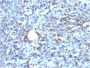

This antibody recognizes a glycoprotein of 110 kDa, which is identified as CD68. It is important for identifying macrophages in tissue sections. It stains macrophages in a wide variety of human tissues, including Kupffer cells and macrophages in the red pulp of the spleen, in lamina propria of the gut, in lung alveoli, and in bone marrow. It reacts with myeloid precursors and peripheral blood granulocytes. It also reacts with plasmacytoid T cells, which are supposed to be of monocyte/macrophage origin. It shows strong granular cytoplasmic staining of chronic and acute myeloid leukemia and also reacts with rare cases of true histiocytic neoplasia. Lymphomas are negative or show few granules. Primary antibodies are available purified, or with a selection of fluorescent CF® Dyes and other labels. CF® Dyes offer exceptional brightness and photostability. Note: Conjugates of blue fluorescent dyes like CF®405S and CF®405M are not recommended for detecting low abundance targets, because blue dyes have lower fluorescence and can give higher non-specific background than other dye colors.

Positive Control

U87MG, Tonsil, Lymph Node or Spleen.

IF (verified), IHC, FFPE (verified), WB (verified)